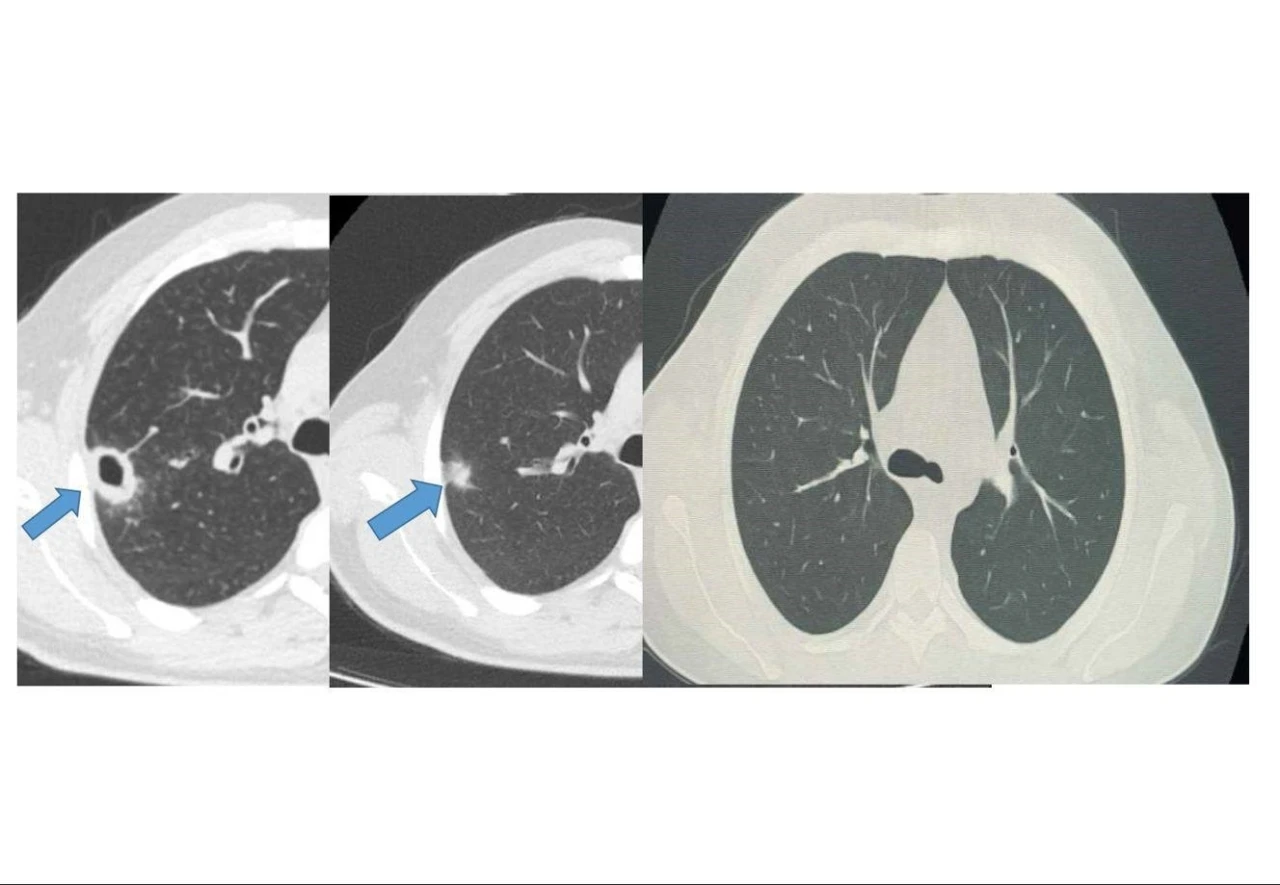

Bayburt Devlet Hastanesine öksürük ve balgam şikayetiyle başvuran 50 yaşındaki hastanın akciğerinde kitle benzeri bir doku tespit edildi. Yapılan tetkikler sonucu ciddi bir hastalık olmadığı belirlenen hasta, erken tanı ve doğru tedavi sayesinde sağlığına kavuştu.

Göğüs Hastalıkları Uzmanı Uzm. Dr. Hilal Sayma tarafından muayene edilen hastaya ileri tetkik amacıyla bronkoskopi işlemi uygulandı. Bronkoskopi sonucunda lezyonun kanser veya tüberküloz gibi ciddi hastalıklarla ilişkili olmadığı belirlenerek, hasta için uygun tedaviye başlandı.

İki haftalık tedavi sürecinin sonunda yapılan kontrollerde lezyonun neredeyse tamamen gerilediği görüldü. Sağlığına kavuşan hastanın taburcu edildiği ve durumunun iyi olduğu öğrenildi.